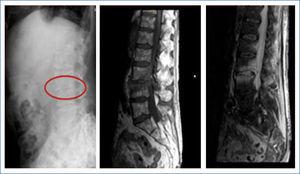

Varón de 63 años con antecedentes de DM de larga evolución, hepatopatía por virus de hepatitis C, tuberculosis pulmonar, arteriopatía periférica y ERC estadio V en hemodiálisis, al que se le realizó trasplante renal con recidiva de la disfunción renal, reiniciando hemodiálisis por CPY. Acude a Urgencias por cuadro de 5 días de evolución de dolor lumbar intenso de características aparentemente mecánicas asociado a episodios de fiebre de 38 ºC en algunas ocasiones. En la analítica destaca leucocitosis elevada con desviación izquierda, proteína C reactiva de 12,9 y procalcitonina de > 10. Se realiza una gammagrafía ósea, donde no se observan focos hipercaptantes sugerentes de proceso infeccioso-inflamatorio; sin embargo, en la resonancia magnética se objetivan imágenes compatibles con ED L3-L4 con absceso paravertebral (figura 1). Los hemocultivos resultan positivos para Staphilococcus epidermidis sensible a vancomicina, linezolid y cotrimoxazol. Se asocia el uso de corsé lumbar, tratamiento analgésico con parches de fentanilo y cobertura antibiótica, inicialmente con vancomicina intravenosa en diálisis durante 3 meses, que se cambió a daptomicina por persistencia de la sintomatología clínica. Tras casi 6 meses de tratamiento, se consiguió mejoría clínica significativa, negativización de los hemocultivos y casi normalización de los reactantes de fase aguda. Actualmente el paciente continúa en hemodiálisis sin otra complicación significativa.

Figura 1. Radiología e imágenes de resonancia magnética